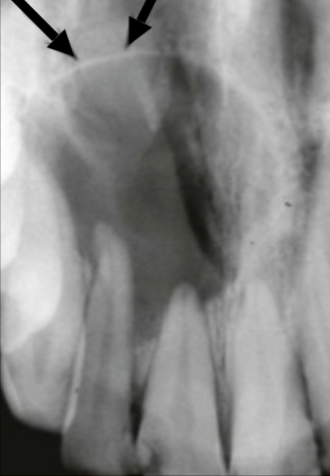

Describe this Radicular Cyst

Epicenter at apex (usually evidence of dental disease or trauma)

Well-defined, corticated

Lucent

Circular

Resorption, Displacement, Expansion (effect on adjacent structures)